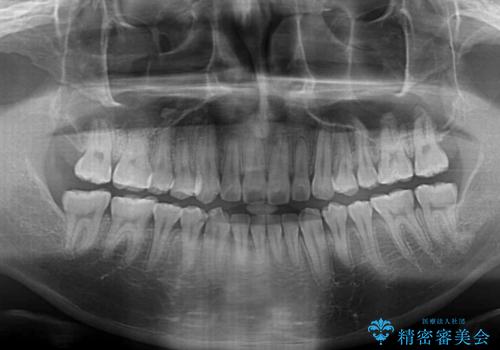

八重歯と前歯のクロスバイト ワイヤー装置で短期間矯正

治療開始の頃は、食事や歯磨きが慣れず、装置が頻繁に脱落しましたが、2,3ヶ月ほどで慣れ、その後は1年ほどで治療を終えることができました。